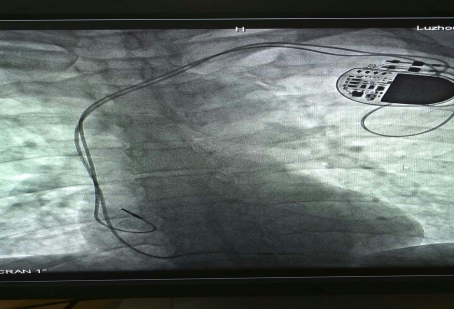

已安裝好的磁共振兼容起搏電極

近年來,隨著醫(yī)學科技的進步帶動了起搏器的一次次革新,磁共振檢查“大門”已經(jīng)向起搏器患者開放,可以說全面“解禁”磁共振檢查的時代到來了。通過對材料和工藝在內(nèi)的一系列技術改進,有了可以兼容的磁共振起搏系統(tǒng),包括磁共振兼容脈沖發(fā)生器和磁共振兼容起搏電極。

?“磁共振兼容起搏系統(tǒng)適用于所有起搏器植入術患者。雖然現(xiàn)在磁共振兼容性起搏器已經(jīng)用于臨床,但是由于整套系統(tǒng)的昂貴價格及醫(yī)保支付等原因,一部分患者因為經(jīng)濟原因暫時不能植入磁共振兼容全套系統(tǒng)。”朱彬醫(yī)師表示,心臟起搏器系統(tǒng)包含脈沖發(fā)生器和起搏電極兩部分,起搏電極的拔除和更換手術較復雜并且具有一定的風險,而單純的脈沖發(fā)生器更換術則比較簡單。因此,對暫時不能植入磁共振兼容全套系統(tǒng)的患者,可以先植入磁共振兼容起搏電極導線,等到將來各方面條件成熟或需要做磁共振檢查時再直接更換脈沖發(fā)生器。此種方案可以滿足未來患者接受磁共振檢查的潛在需求。